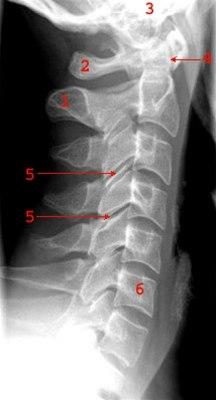

Normalt sidebilde av cervicalcolumna (ryggsøylen, nakke)

- Prosessus spinosus

- Atlas

- Skallebasis

- Dens axis

- Intervertebralledd (fasettledd)

- Virvelkorpus C6